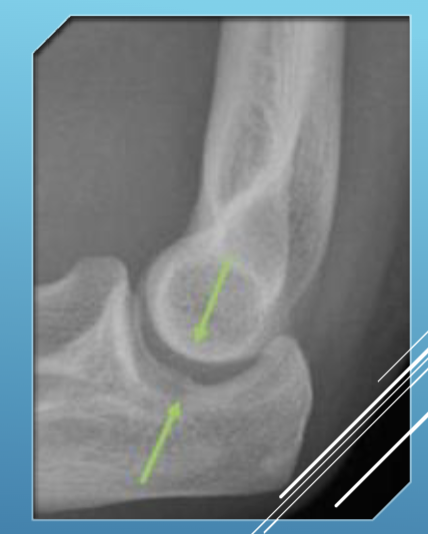

Drop Sign

The elbow joint space being larger than 4 mm of space indicates arthritis